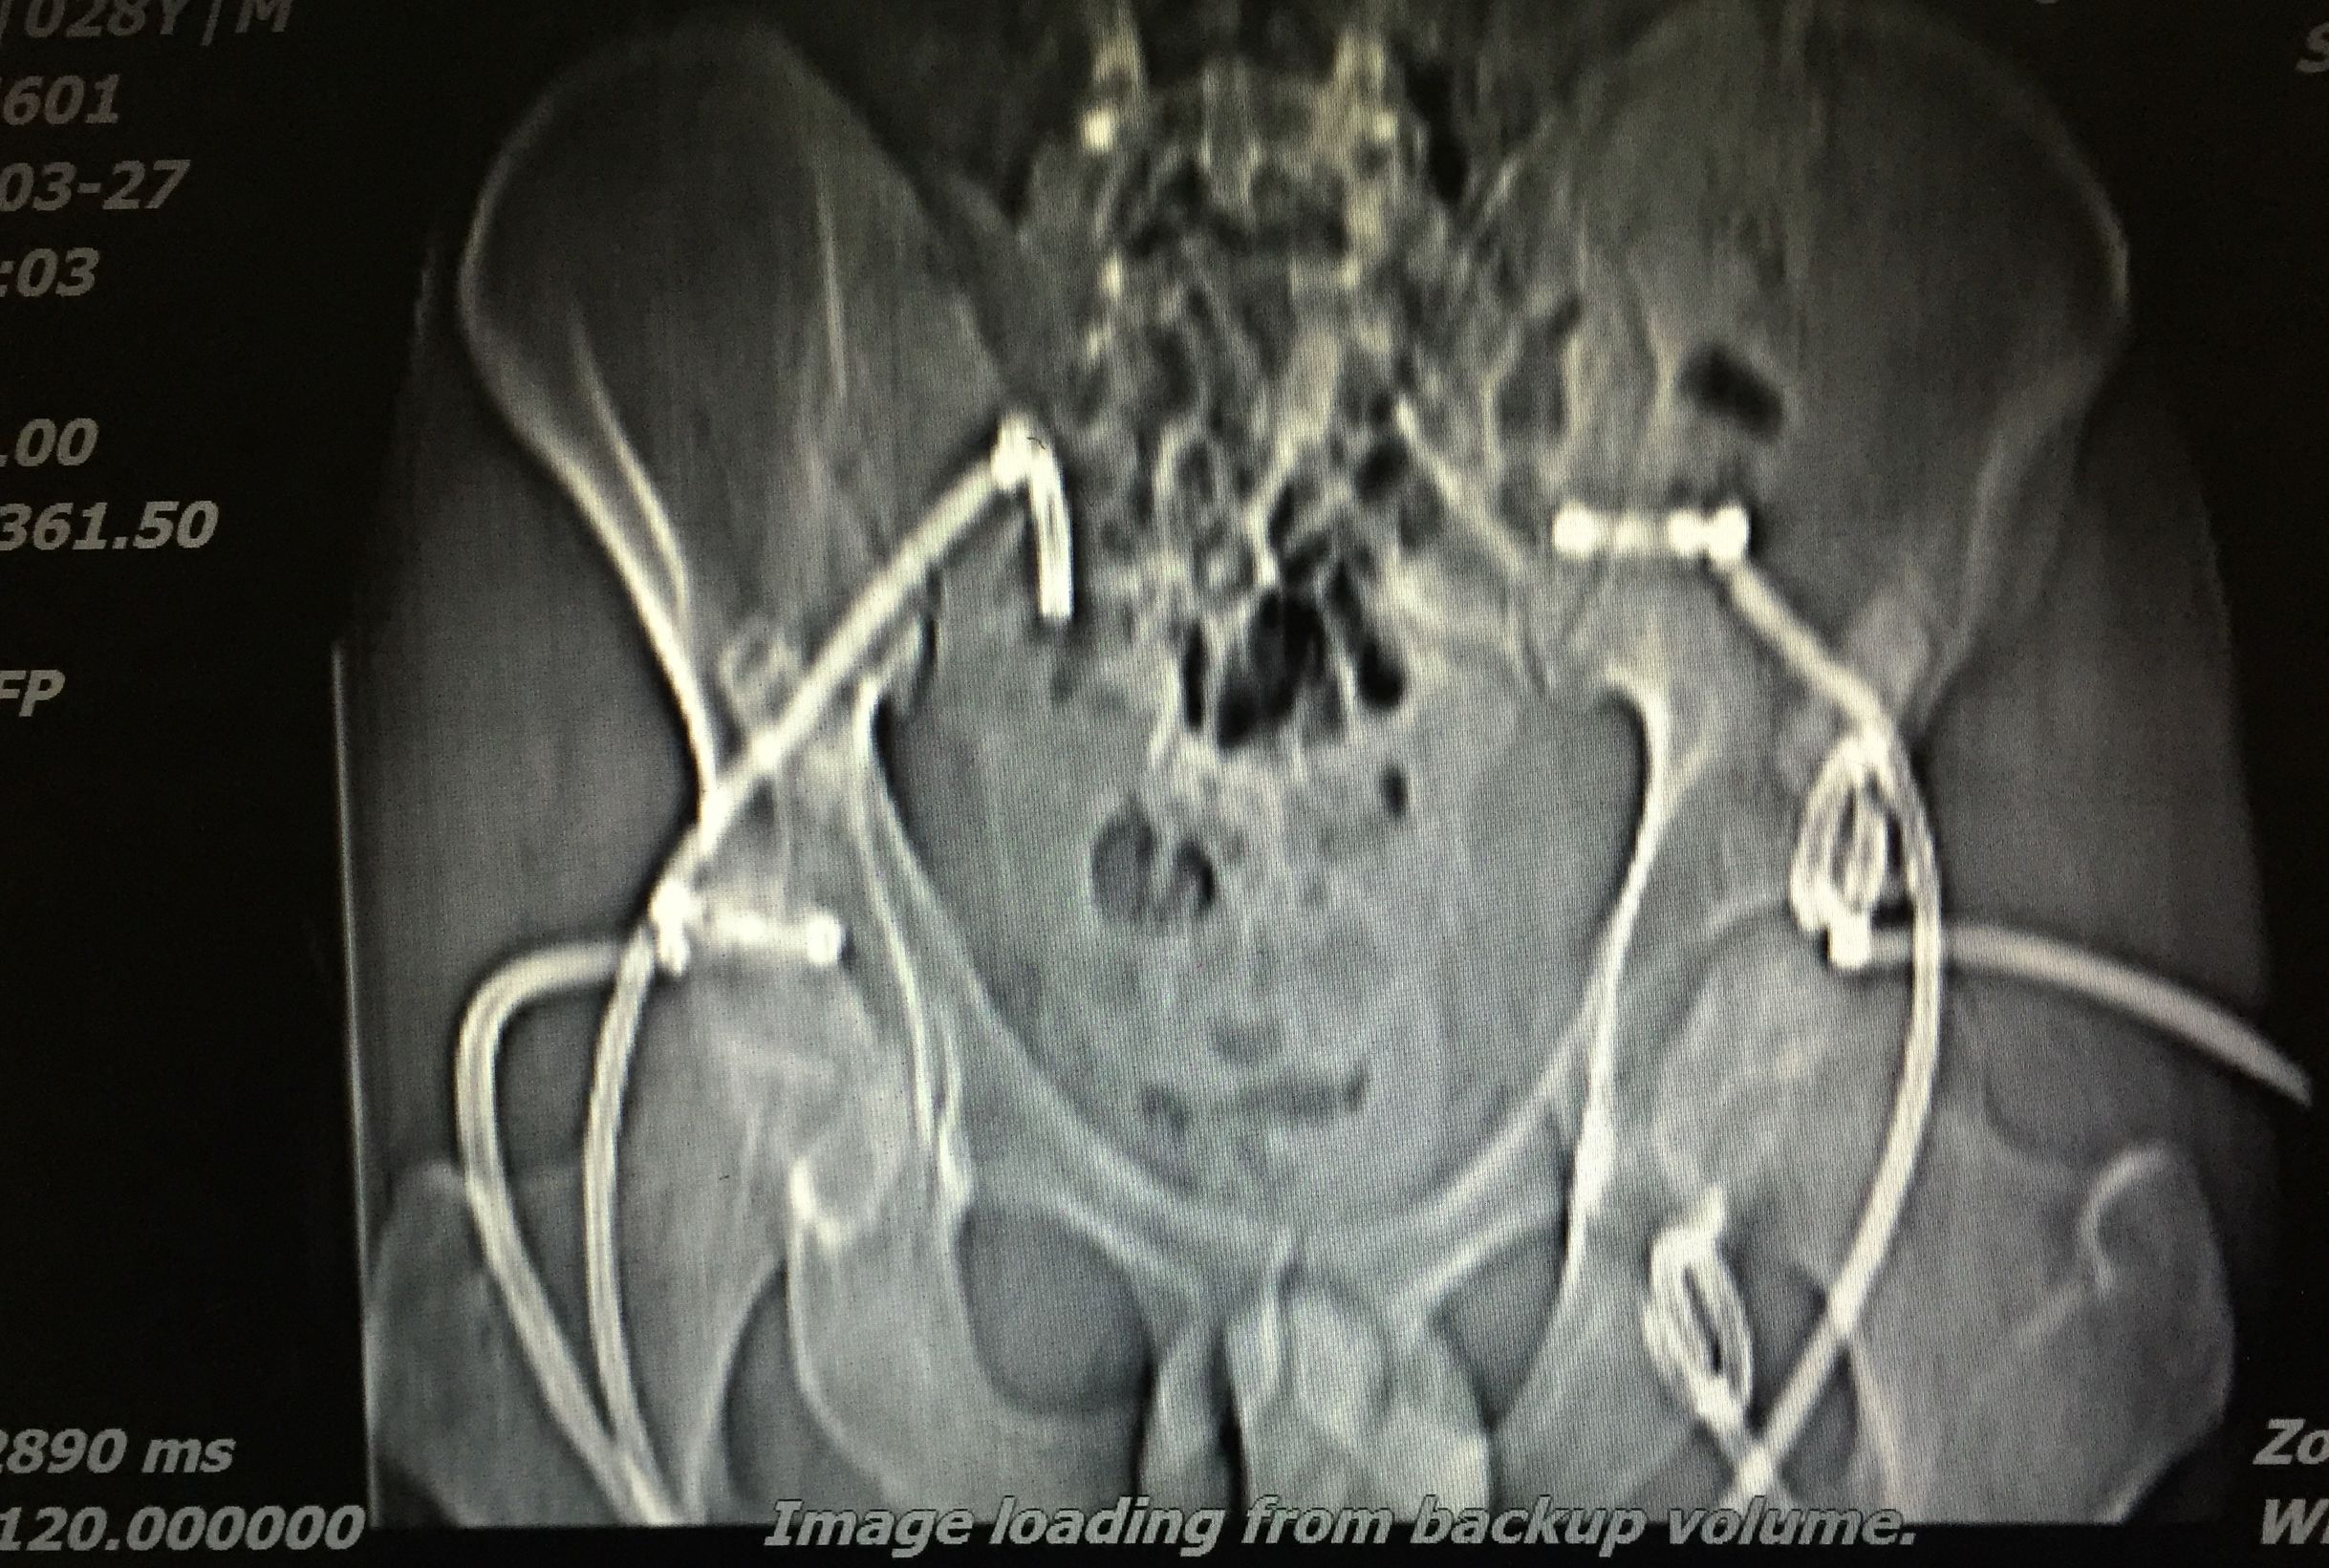

患者 29岁 盆腔及大腿根部多发结核脓肿(如图)

治疗方案充分穿刺置管引流+抗痨治疗

在门诊进行CT引导下穿刺引流术,植入五根引流管(如图白色条状物)